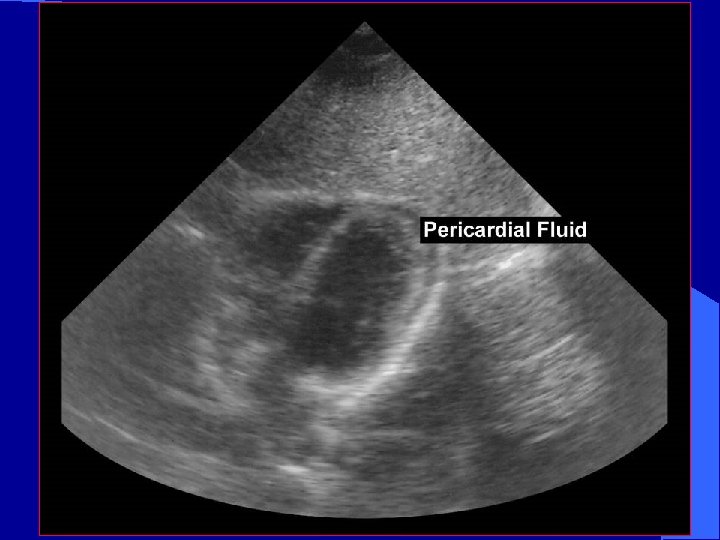

Penetrating Cardiac Trauma l Pericardial effusion – May develop suddenly or surreptitiously – May exist before clinical signs develop l Salvage rates better if detected before hypotension develops

Pericardial Fluid fluid

Occult Penetrating Cardiac Trauma l Observation unreliable l Subxiphoid window – Invasive – 100% sensitive, 92% specific – Negative exploration rates (as high as 80%) l Ultrasound reliable indicator of even small pericardial effusion

Trauma Study The role of ultrasound in patients with possible penetrating cardiac wounds: a prospective multicenter study. Rozycki GS: J Trauma. 1999 Pericardial scans performed in 261 patients l Sensitivity 100%, specificity 96. 9% l PPV: 81% NPV: 100% l Time interval BUS to OR: 12. 1 +/- 5. 9 min l

Avoid Pitfalls l Normal echo does not definitively rule out major pericardial injury l Repeat echo with clinical picture l Epicardial fat pad may easily be misinterpreted as “clot” l Hemothorax may be confused with pericardial effusion